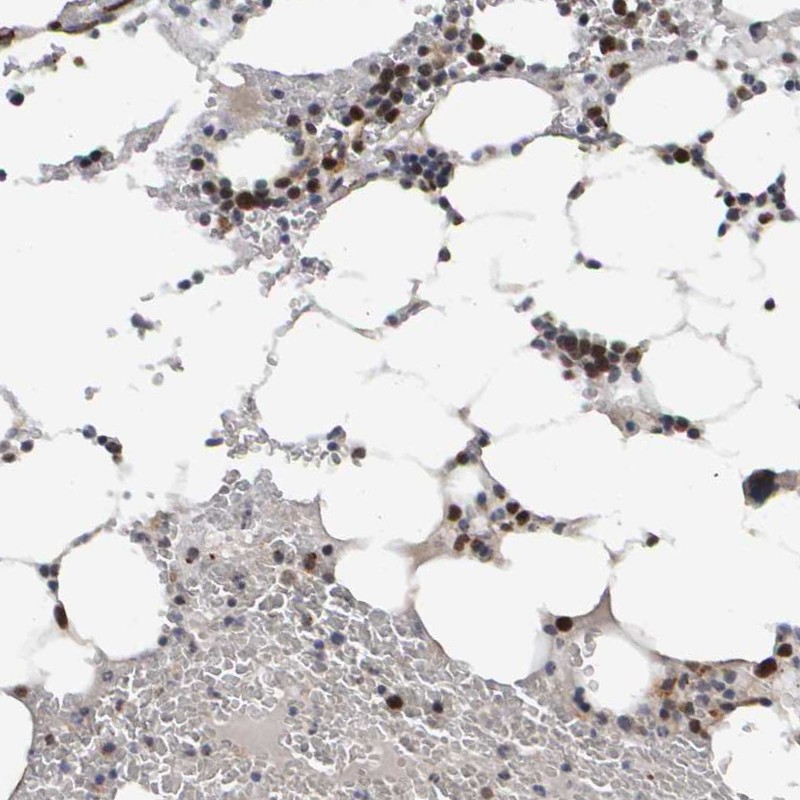

Immunohistochemical staining of human bone marrow shows immune cell positivity in hematopoietic cells.